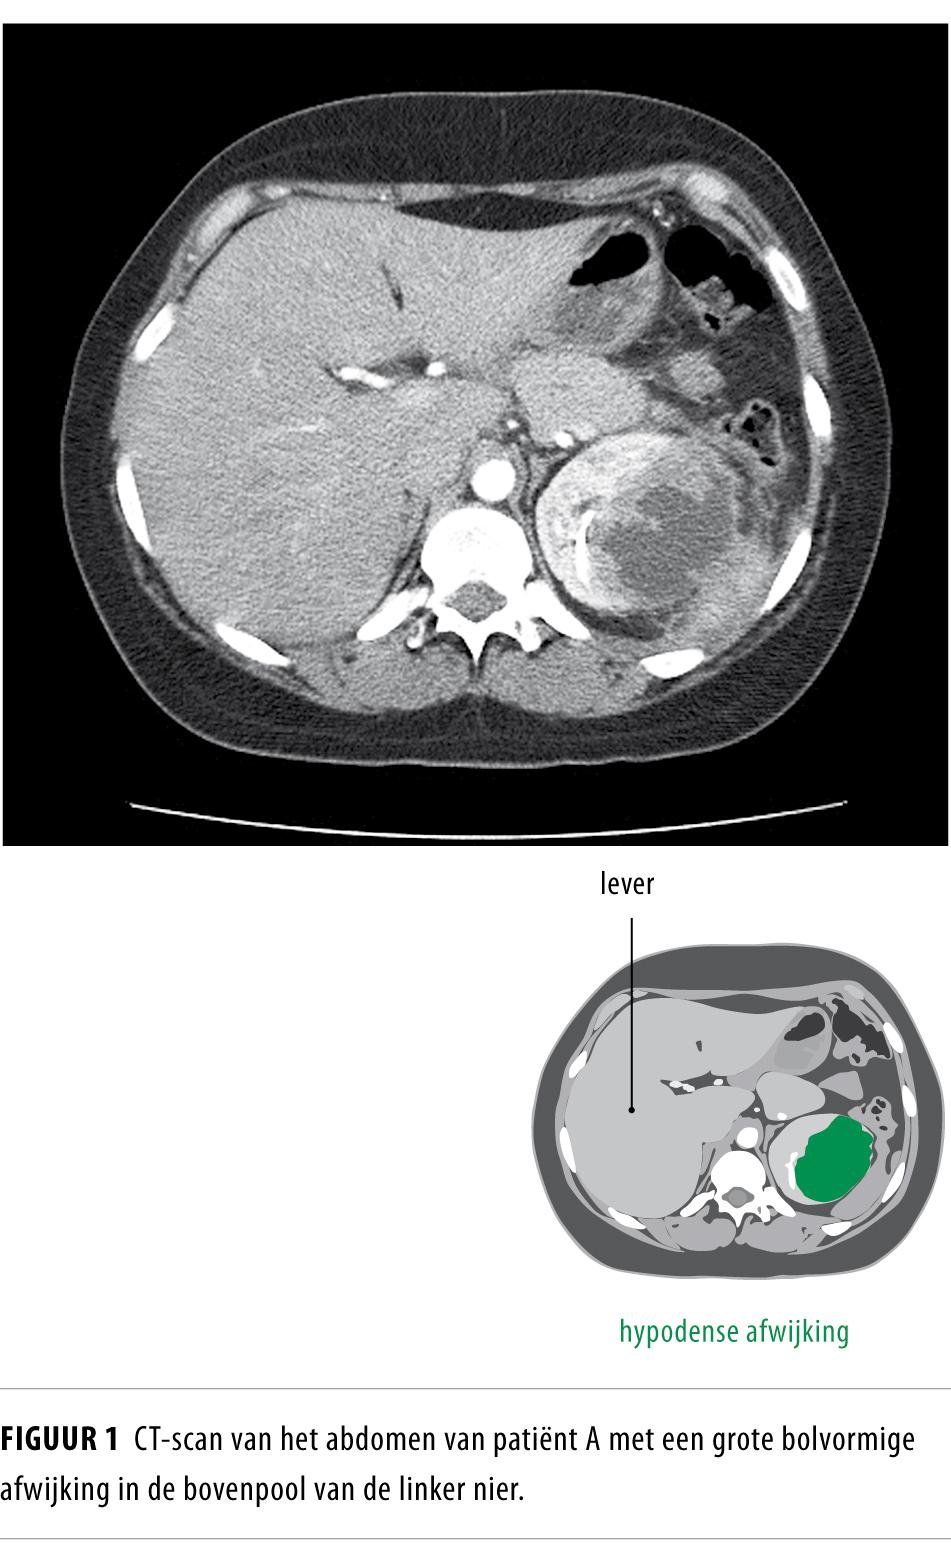

Wij beschrijven 2 patiënten met moeilijk te behandelen en frequent recidiverende urineweginfecties. De diagnose ‘xanthogranulomateuze pyelonefritis’ is gesteld op basis van het beeldvormend onderzoek waarbij een diffuus gezwollen nier en urolithiasis werden gezien. Beide patiëntes konden succesvol worden behandeld door drainage van de aangedane nier met een ureterale dubbel-J-katheter en antibiotica.